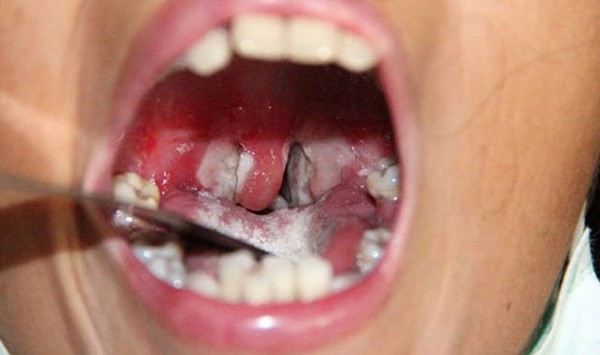

Khi khám, bác sĩ có thể thấy có giả mạc trắng ngà hoặc màu xám dính chặt vào xung quanh tổ chức viêm, nếu bóc ra sẽ bị chảy máu. Cho giả mạc vào cốc nước dù khuấy mạnh cũng không tan. Còn giả mạc mủ sẽ bị hòa tan hoàn toàn trong cốc nước. Vùng niêm mạc xung quanh giả mạc bị xung huyết.

Thứ hai, bệnh ở vùng bạch hầu họng và amidan sẽ có biểu hiện đau rát cổ họng, chán ăn, sốt nhẹ, mệt mỏi nhiều. Sau khoảng 2-3 ngày, vùng amidan hoặc hầu họng sẽ xuất hiện những đám hoại tử tạo thành lớp giả mạc màu trắng xanh, dai và dính chắc.

Thể nặng nhất là bạch hầu thanh quản. Bệnh nhân thường tiến triển nhanh nhất, đặc biệt là trẻ em. Người bệnh thường sốt, khàn giọng, ho to và nhiều; khám có thể thấy hình ảnh nhiều giả mạc tại thanh quản.